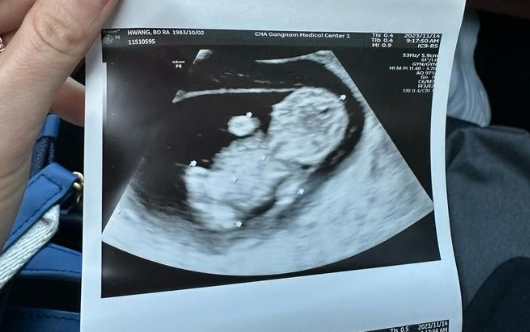

배우 황보라 씨가 출산 후 겪은 고통과 의료 파업과 관련된 오해에 대해 솔직하게 털어놨습니다. 그녀는 지난 5월 아들을 출산하며 제왕절개 수술을 받았고, 이 과정에서 겪은 고통과 이에 대한 자신의 발언으로 인해 많은 논란이 일었습니다. 이번 글에서는 황보라 씨의 출산 후 경험과 그에 따른 해명을 중심으로 자세히 알아보겠습니다.

황보라 씨는 "의료 파업 때문이라는 부적절한 표현을 사용한 것에 대해 신중하지 못한 점을 사과드린다"고 말하며, 담당 의료진과 병원 관계자들에게도 죄송한 마음을 전했습니다. 그녀는 앞으로 더 신중하게 발언할 것을 약속했습니다. 황보라 씨는 난임을 겪고 있던 중 시험관 시술을 4차례 시도한 끝에 임신에 성공했습니다.

그녀의 임신과 출산 소식은 많은 이들에게 큰 축하를 받았습니다. 황보라 씨는 "난임 극복부터 출산 과정, 그리고 새 생명의 탄생까지 축복해 주신 많은 분들께 감사의 말씀을 전합니다"라고 감사의 인사를 전했습니다. 한편, 보건복지부는 7월부터 제왕절개 등 분만 시 무통 주사와 페인버스터를 병용할 수 없다는 급여 기준 개정안을 행정예고 했습니다.